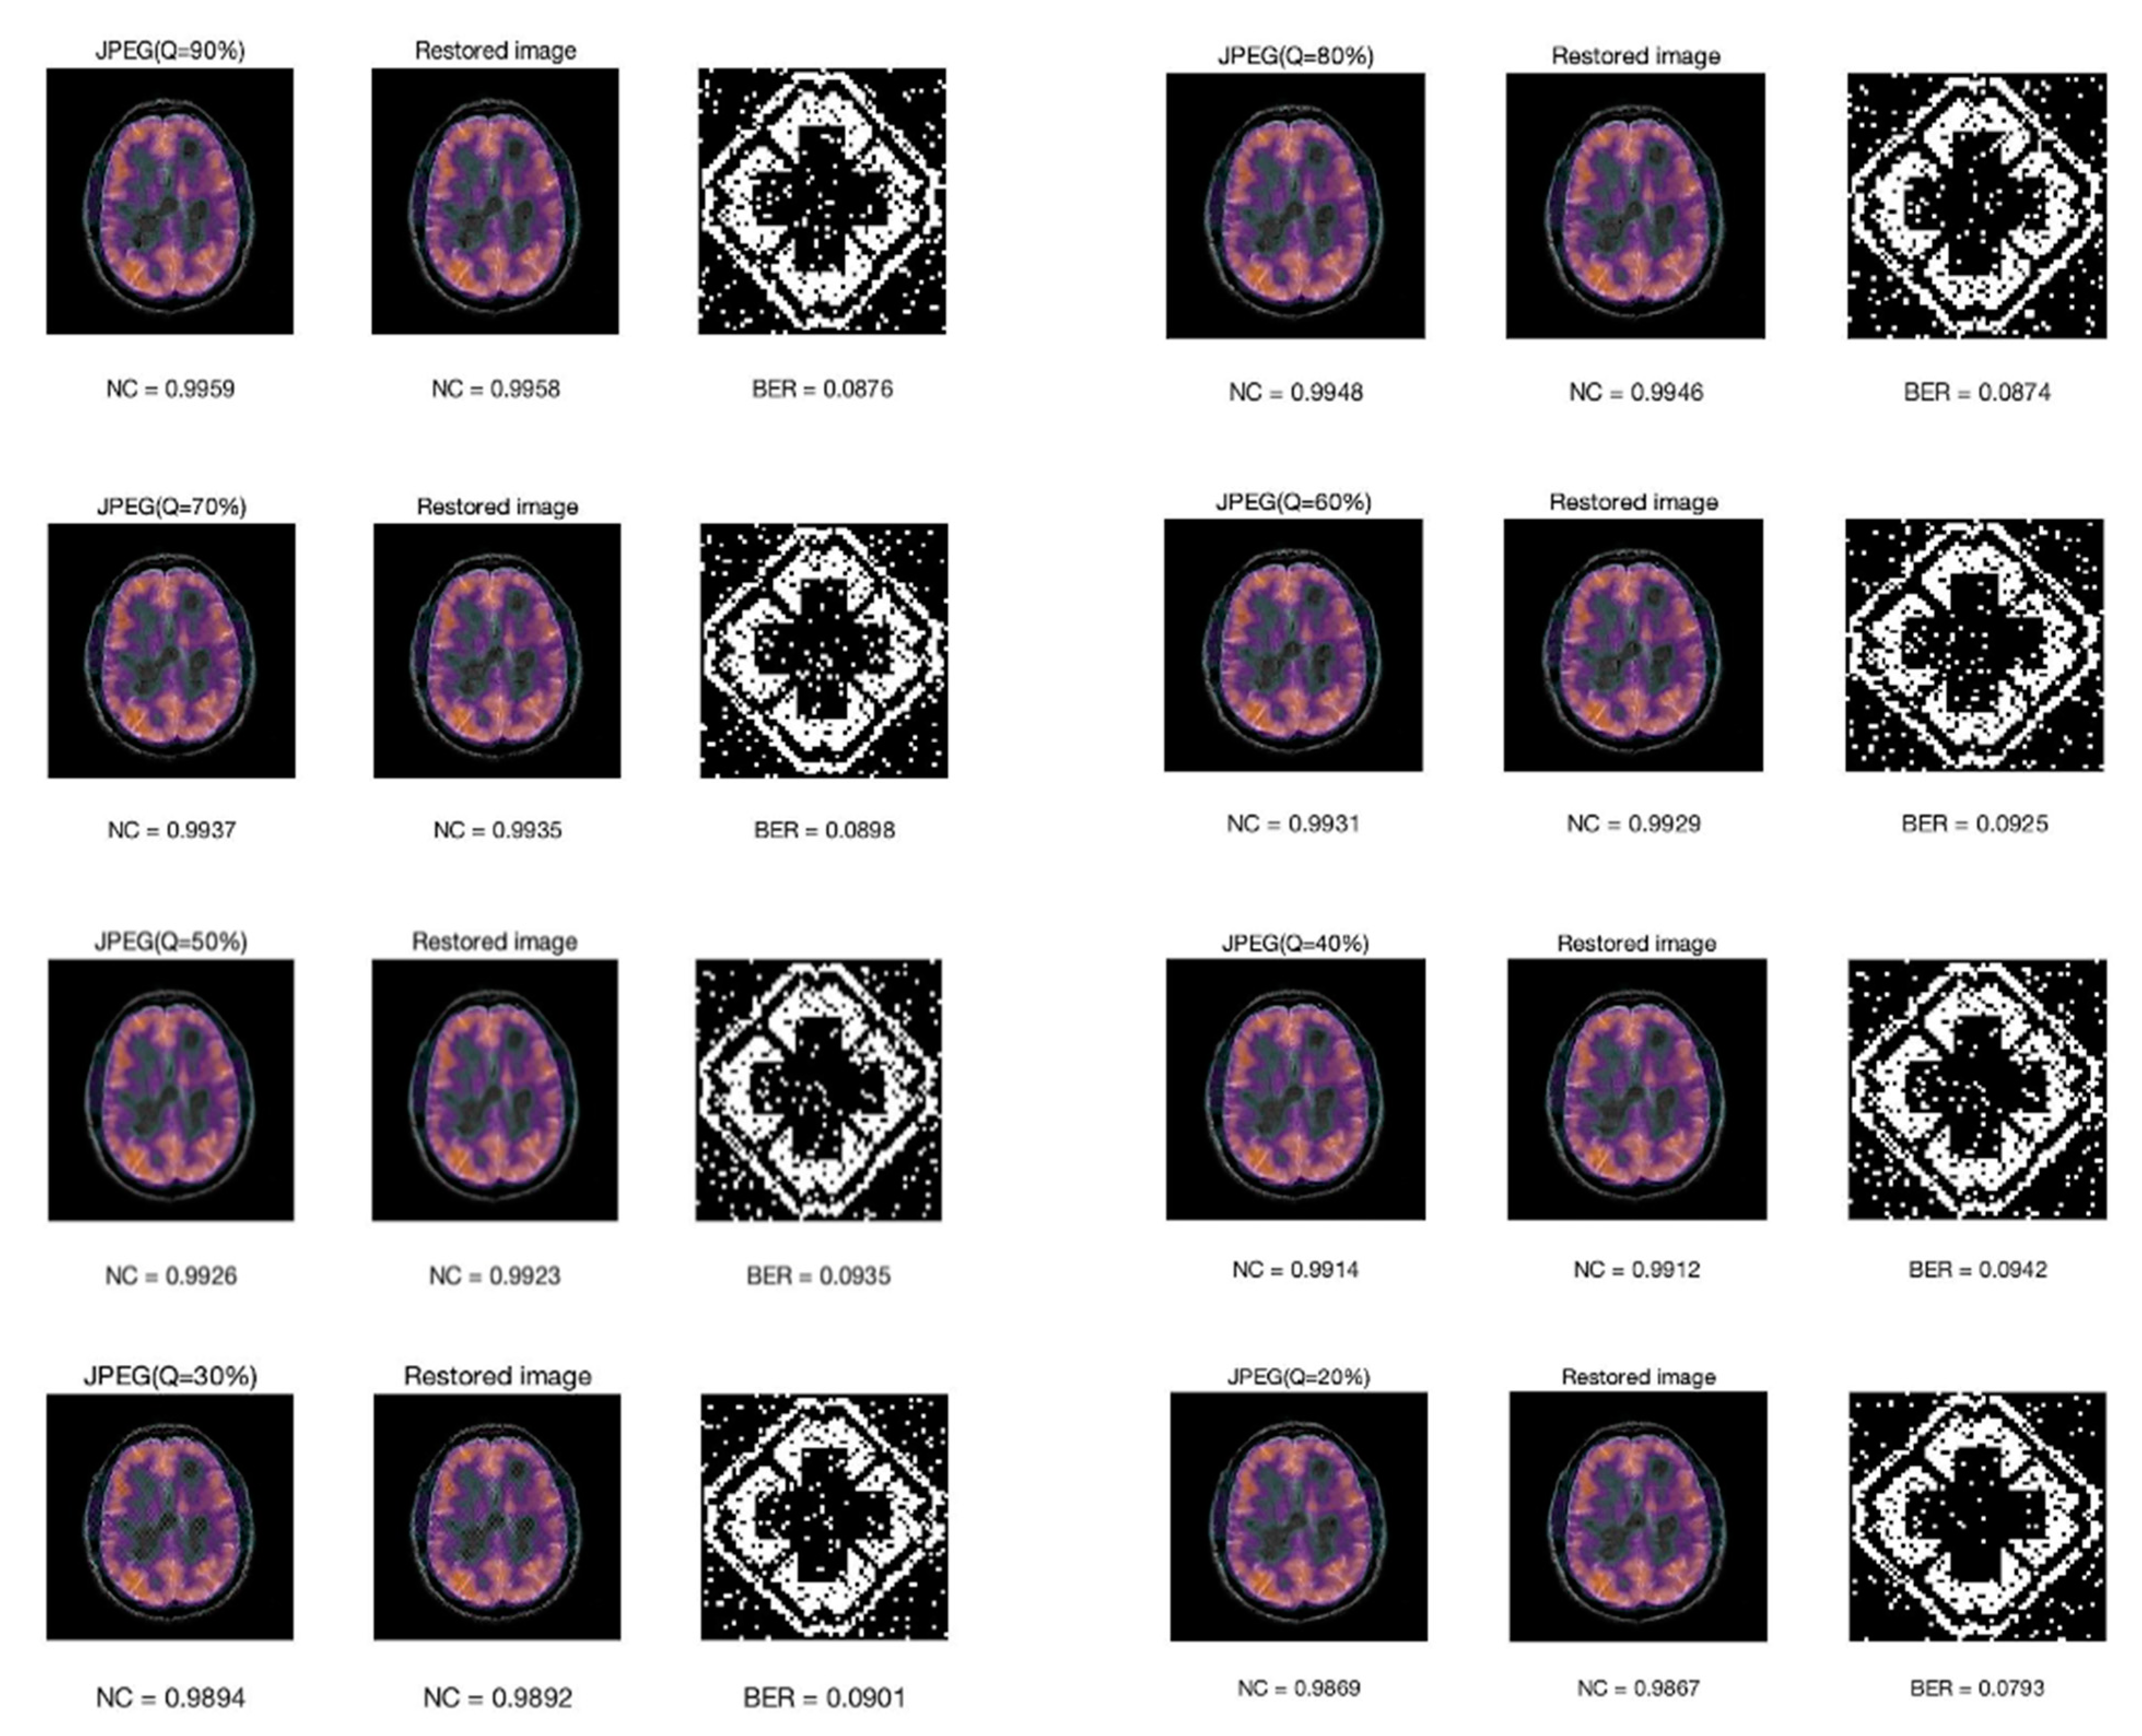

Figure 13 shows the NC value of the compressed image, the recovered image, the extracted watermark image, and its bit error rate under different JPEG compression factors. Note that the scheme is robust to JPEG compression. It is surprising to see that the worst quality JPEG at 20% yielded the smallest BER. In fact, it is not that 20% compression yields better results, but that they all keep in the same level at about 0.08–0.09. The BER of JPEG at 20% is 0.793 in our experiment, which is closely related to the images we use. Whether their BER can be kept at the same level is related to the embedding scheme. In our research, the embedded watermark is represented by the coefficient relationship between each band after DWT transformation and the relationship between one block and the next. After JEPG compression, the image quality is declined. Take the NC value for example, NC is smaller after compression, but there is not much loss of the relationship between block and sub-band, so the watermark can still be extracted precisely. However, for attacks that destroy the relationship between block and sub-band, such as Gaussian noise, the BER is relatively high, which is about 0.3.

Figure 13.

The NC value of the compressed image, the NC value of the recovered image, the extracted watermark image, and its BER under different JPEG compression factors.